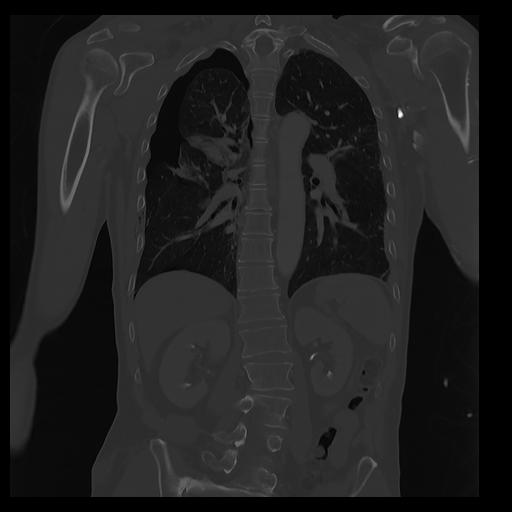

32 PULMON,CE,Coronal,3.000,PULMON,Coronal,